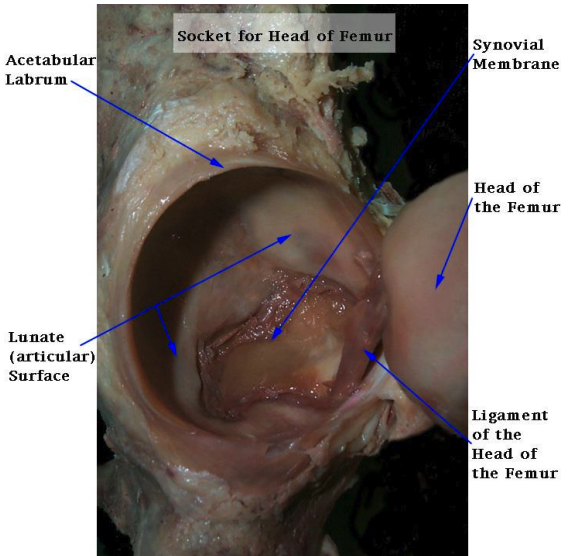

contents of acetabulum

lunate surface: hyaline cartilage, thick superior and anterior (based on WB)

fat pad

ligamentum teres

transverse acetabular ligament: spans acetabular notch and part of labrum, connects lunate surfaces

acetabular labrum

fibrocartilage

deepends socket and increase concavity

negative articular pressure

increases stability

nerve endings: proprioception (joint stability and balance) and pain

clinical relevance: labral tear

when labrum is compromised → friction stresses increases → articular cartilage deterioration → hip osteoarthritis